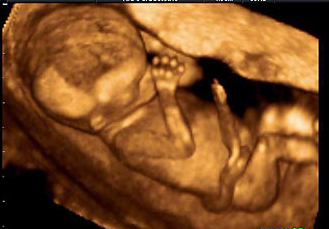

Bu hafta bebeğin ultrasondaki görüntüsüne baktığımızda cinsel organlarının tamamen geliştiği gözlenir ancak cinsiyetinin belli olması için biraz erken bir zaman aralığıdır. Ultrasonla henüz cinsiyeti görülemez. Bu dönemde tiroit hormonları gelişir, saçlar oluşmaya başlar.